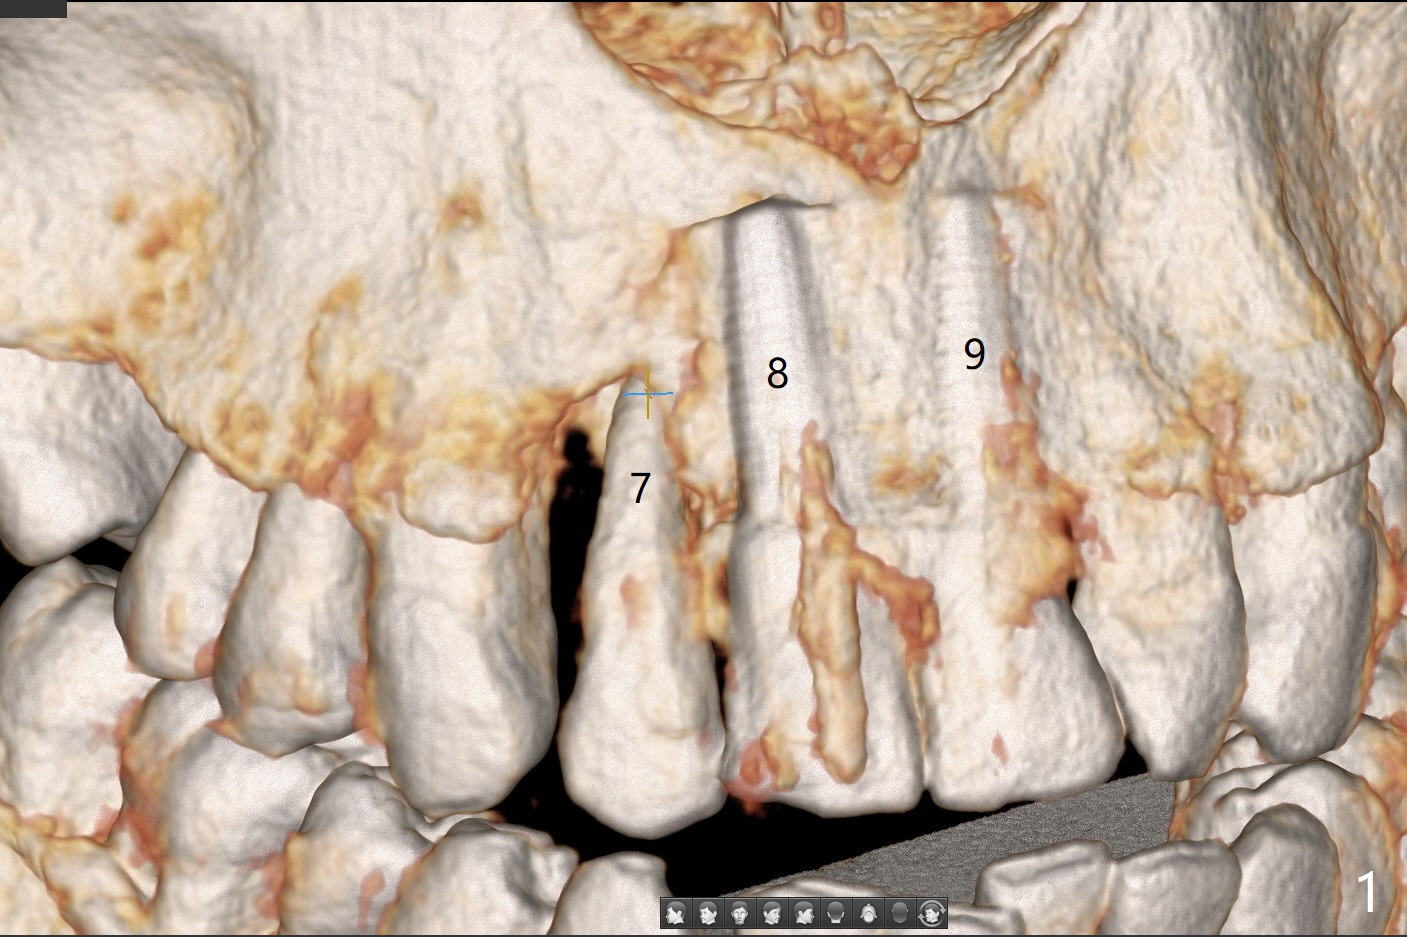

A 58-year-old man recently had sudden pain at #7 with labial plate loss (Fig.1 CT taken 3 years earlier). To avoid the labial placement of the large implants at #8, and 9, the implant at #7 will be smaller and palatally inserted (Fig.2). Fig.3 is a coronal section of 3D image of #7, showing the labial (B) and palatal (P) crests. After extraction (Fig.4 black), the narrow implant is placed between the crests (green). To repair the coronal labial plate, a piece of PRF membrane (Fig.5 blue) is placed inside the socket, followed by sticky bone (red circles). The portion of PRF membrane outside the socket will be flipped palatal, inserted into the abutment with a pre-punched hole and finally tucked underneath the palatal gingiva.